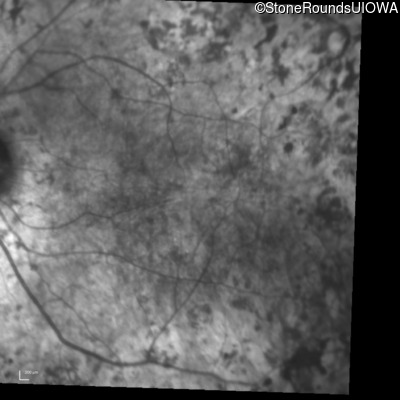

Infrared Fundus Photograph - Right - 20/150

Exemplar